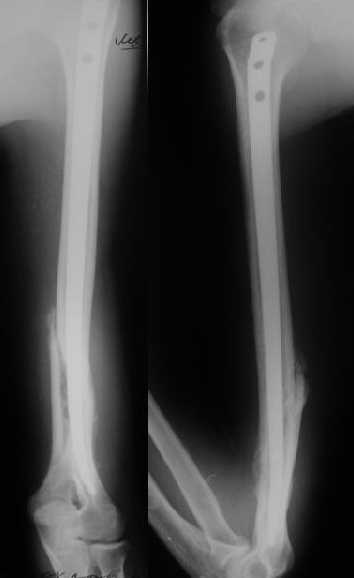

Мы в последние годы все еще используем для переломов такой

локализации эластичные титановые стержни (по мотивам ярославских

разработок, Зверева-Ключевского). Такой стержень можно вводить не

через сухожилие надостной мышцы, а дистальнее.

Снимки до, через 1 и 2 мес. после синтеза.